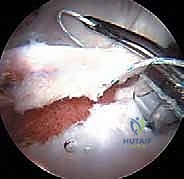

الخطوة 4: معالجة الانحشار ونحت العظام (Osteochondroplasty)

باستخدام أدوات دقيقة وصغيرة جداً (مثل المبرد الآلي)، يقوم الدكتور هطيف بإزالة النتوءات العظمية الزائدة.

* إذا كان الانحشار من نوع "الكامة"، يتم نحت عنق عظم الفخذ ليعود لشكله الانسيابي.

* إذا كان من نوع "الكماشة"، يتم تشذيب حافة الحُق الزائدة.